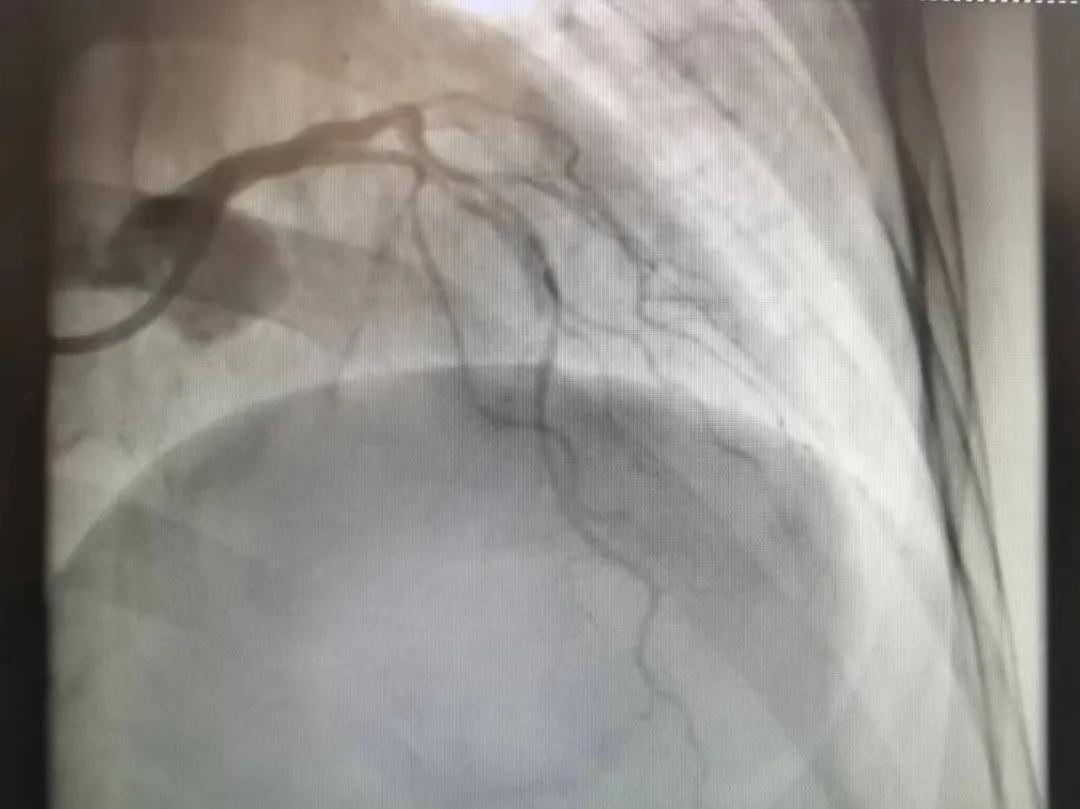

王瑾院長和李慧新主任帶領介入團隊充分評估,決定行前降支冠狀動脈鈣化病變旋磨術,術中應用1.5mm旋磨頭,以15萬-17萬轉/分速度共對病變旋磨3次,累計旋磨時間60秒,后復查造影示鈣化明顯減輕,為后續(xù)操作創(chuàng)造了良好條件,隨后應用預擴張球囊、切割球囊再次處理病變,并順利植入支架1枚,復查造影顯示支架膨脹及貼壁良好,無夾層、血腫、慢血流等情況,手術順利完成。患者術后無不適,胸悶、胸痛癥狀明顯緩解,順利出院。

術后